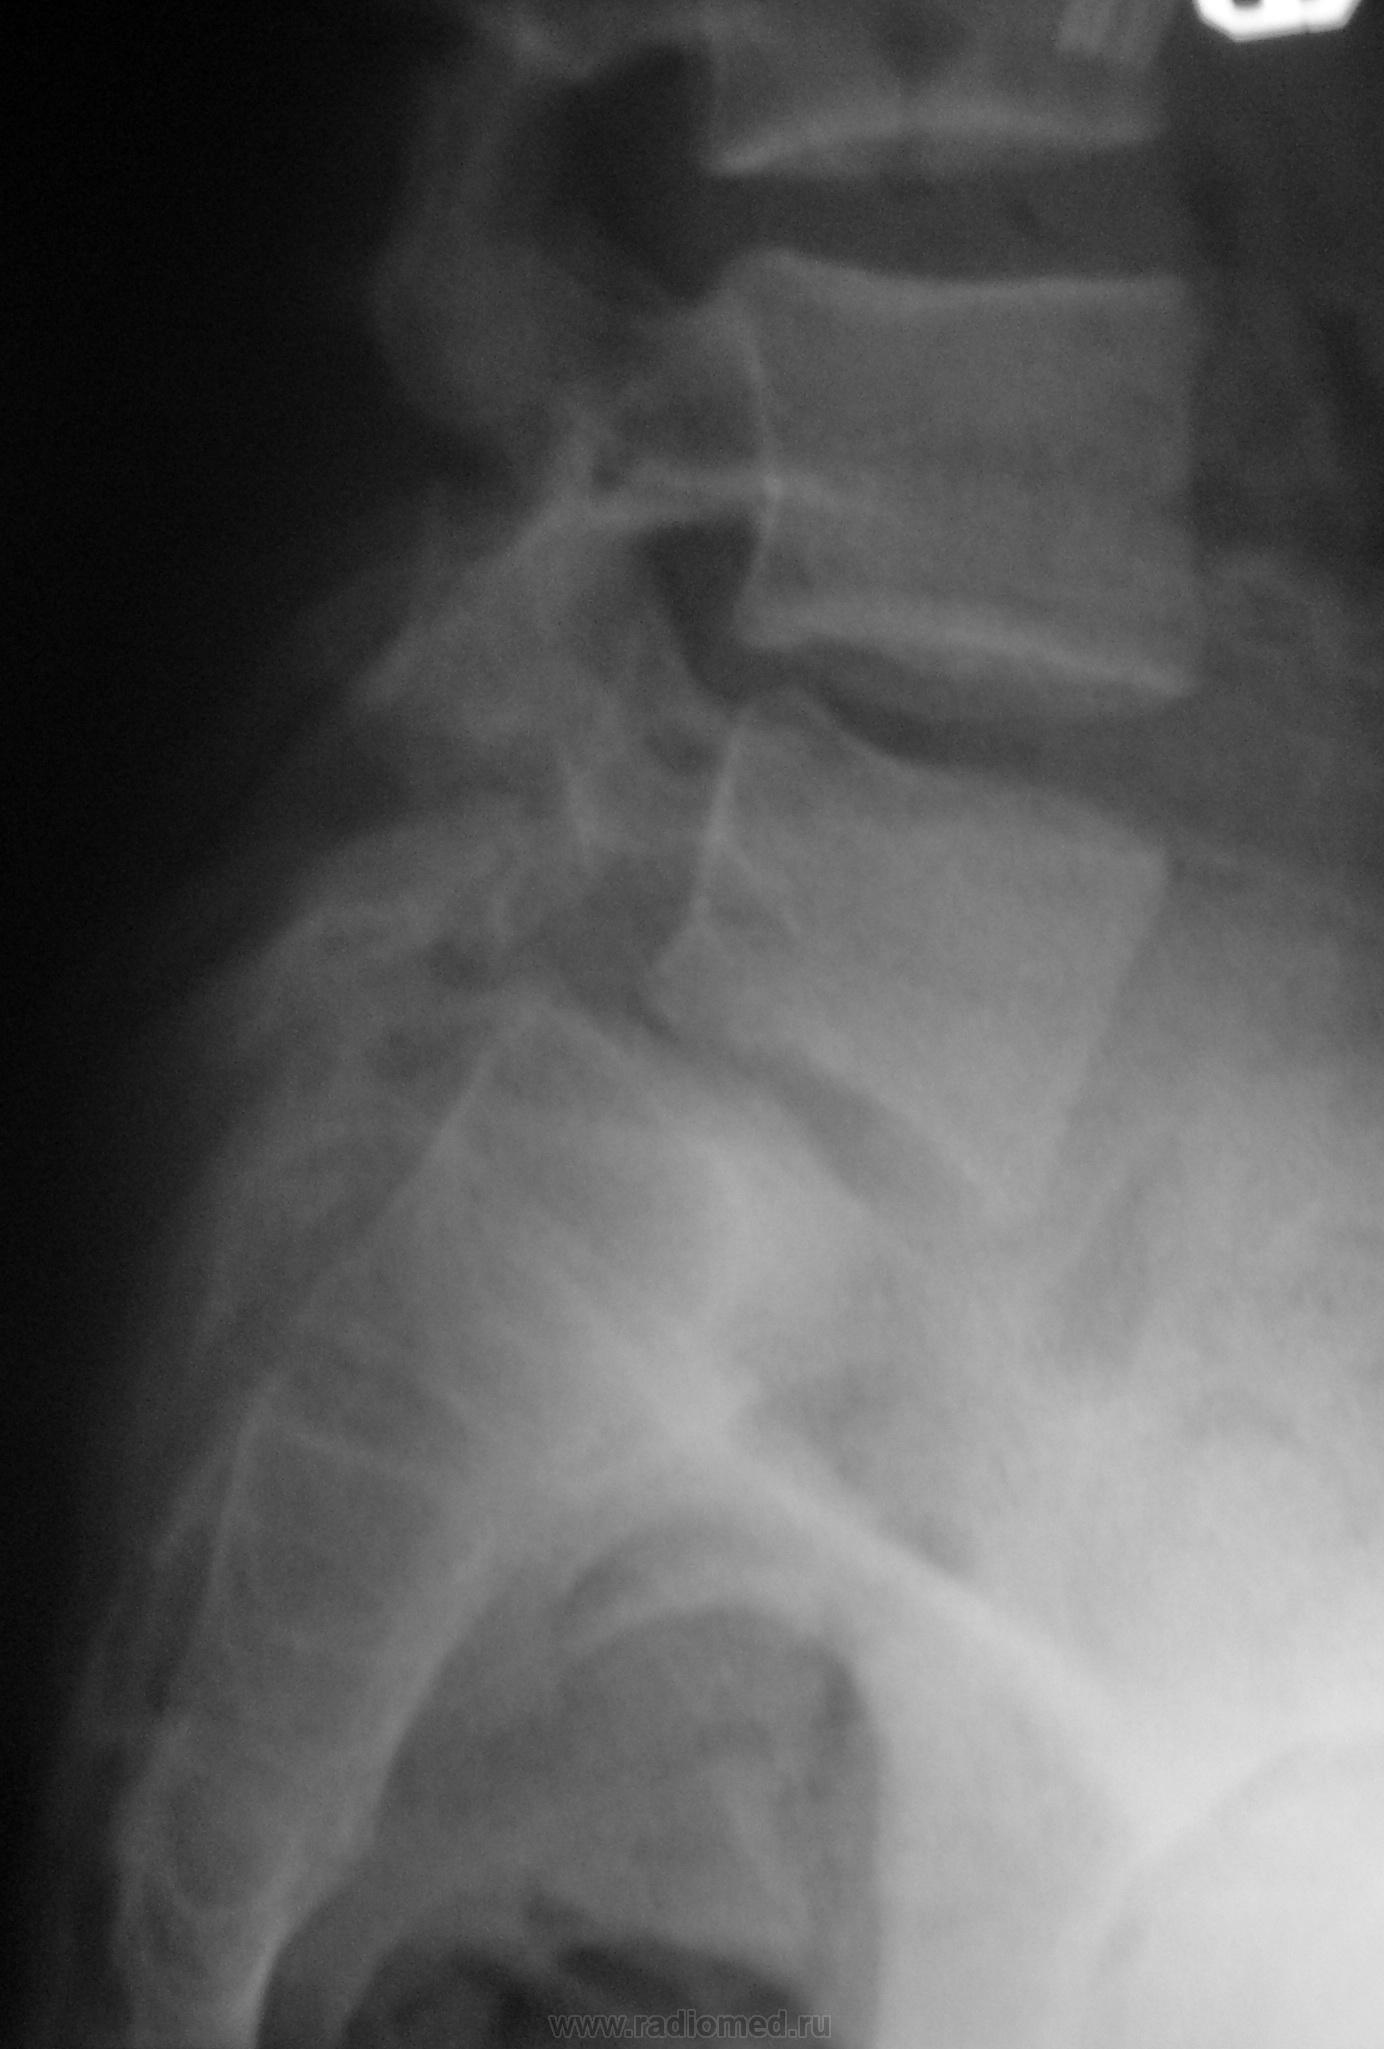

Молодой человек, занимаясь в спортзале, неаккуратно взял вес. Беспокоят боли в пояснице.

Истинный передний спондилолистез I степени и незаращение дужки L5

+1. Spina bifida S1.

На мой взгляд, сложно сказать явился ли листез следствием травмы (гипернагрузки), предыдущих снимков скорее всего нет. но исходя из умозаключения "где тонко, там и рвётся", смею предположить, что причина жалоб пациента находится именно на уровне спондилолистеза. ...правда, как облачить это в форму заключения протокола рентгенографического исследования я не знаю...

Если бы такой листез был следствием однократной гипернагрузки, думаю, что без инвалидной коляски бы не обошлось. Но о дальнейшем занятии таким спортом нужно задуматься.